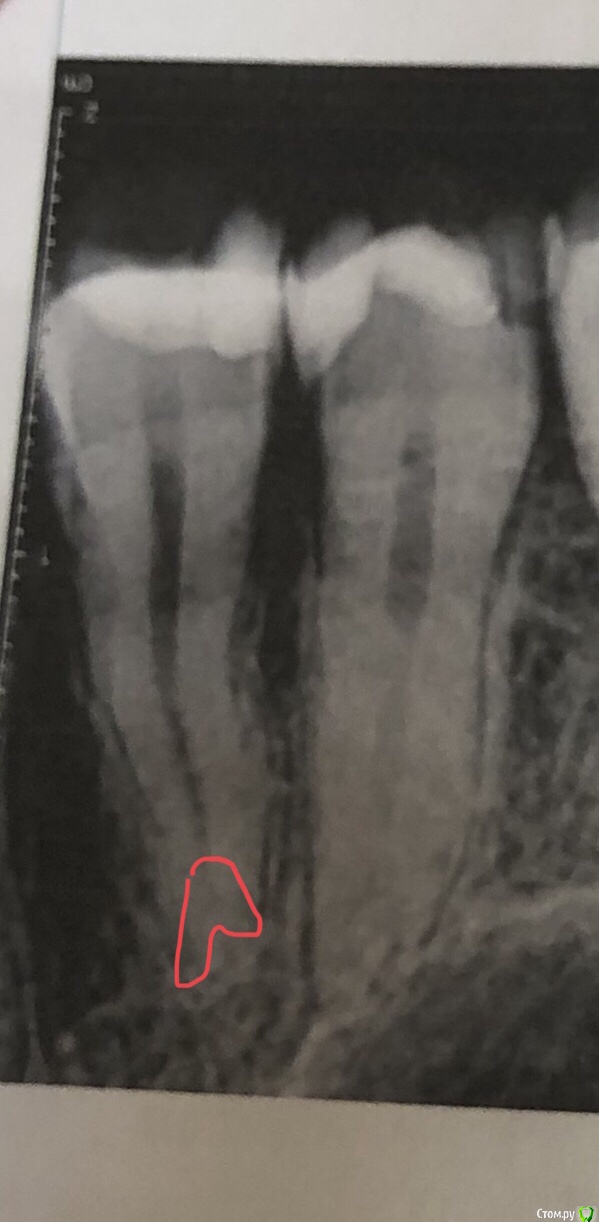

Olga2396 Опубликовано 6 октября, 2019 Поделиться Опубликовано 6 октября, 2019 (изменено) Зуб не болит 4й,но при постукивании чувствителен. Что с боку если постучат, что если постучать на жевательную поверхность.При первом лечении каналов зуб продолжал реагировать на горячее, был крайне чувствителен после горячего,языком было недотронуться. Врач перелечила каналы,боль уменьшилась,при надкусывании не больно, но непонятно почему если постучать неприятно, хотя с другими зубами у которых есть нерв нет неприятного ощущения. + переживаю из за того что выведено за верхушку корня, гуттаперча ли это? Или силлер, пломбировали мне кстати эндометазоном. Надо перелечивать? Или смотреть за состоянием зуба через пол года,будет ли увеличиваться чувствительность или уменьшаться.+ ко всему говорят об удаление нерва из 5го зуба. Зуб чувствителен на холодное,иногда горячее,но не пульсирует,ночных болей нет. Надо ли удалять? Говорят у меня анатомия зубов что нерв близко расположен к поверхности зуба,но при препарировании не была вскрыта пульповая камера и сказали дентин плотный, но 5 зуб чувствителен на холодное,но не больно,обезболивающее не пью и проходит сразу же. Я уже устала с этими зубами, вроде пролечила, а неприятных ощущения есть. 4й зуб пролечен уже как месяц. 5й пока не удаляют нерв смотря за динамикой,есть ли боли нет. Иногда сам как будто микротоком мимолетно стрельнет, ощущения как если бы укололи палец,не больно и пройдётсразу же. Не пульсирующая.1. До удаления нервов 4й5й зуб2. После удаления нерва,первая попытка (боли,чувствительностью горячее)3,4- после 2го лечения в разных боковых проэкциях снимок. Состояния на данный момент 4 и 5 зубаНа 5 снимке красным я отметила потемнее похоже на доп.ветвь канала. На снимках 3,4 есть это ответвление. Это доп. Канал?или особенность снимка? Изменено 6 октября, 2019 пользователем Olga2396 Ссылка на комментарий

red_butler Опубликовано 10 октября, 2019 Поделиться Опубликовано 10 октября, 2019 Четвертый пролечен достойно, дискомфорт при постукивании должен пройти. Зуб обязательно восстановите искусственной коронкой. Пятый, доктор оставил часть старой пломбы? По рентгену необходимости лечения каналов не увидел. По снимку есть вопросы по контактным пунктам между пятым и шестым - пломбировочный материал в межзубном промежутке, на шестом, его нужно убрать. Если боли в пятом быстро проходящие, и не исчезнут, то ставить вопрос о повторном лечении Ссылка на комментарий